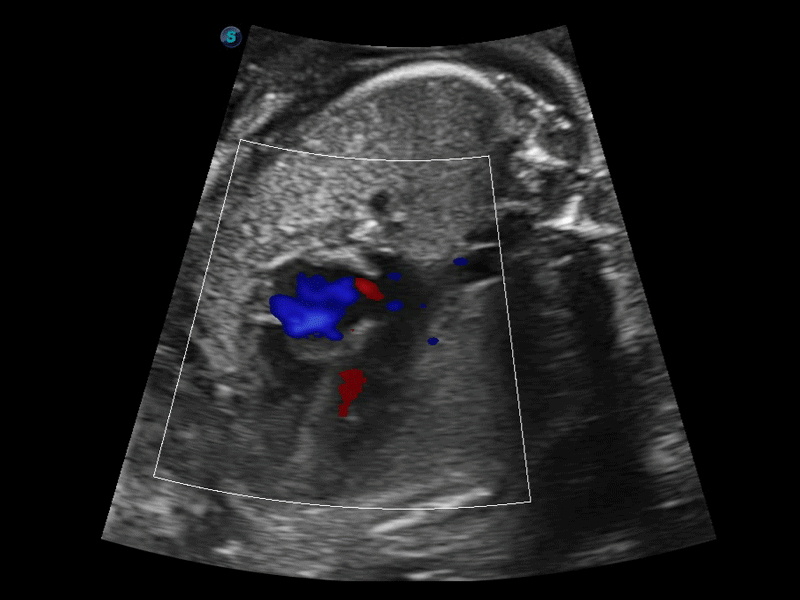

開立醫(yī)療通過不斷的技術(shù)創(chuàng)新,為大眾的生命健康提供持續(xù)關(guān)愛。P12 Plus采用全新一代超聲成像平臺(tái),新平臺(tái)旨在將真實(shí)還原組織解剖結(jié)構(gòu)作為首要目標(biāo)。平臺(tái)采用全新集成化硬件模塊,搭載新一代芯片,系統(tǒng)性能得到大幅提升,為您的診斷提供了豐富的臨床信息。優(yōu)異的圖像表現(xiàn),豐富的探頭配置,全面的應(yīng)用功能,為您日常診斷提供了可靠的助手。

彩色多普勒超聲診斷系統(tǒng)